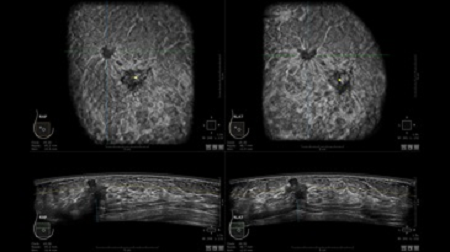

• Получение объемных 3D изображений с возможностью покадрового просмотра

• Получение изображений в поперечной плоскости (в реальном времени) и в коронарной плоскости (статическая, для указания нахождения соска)

• Отображение объемных 3D ультразвуковых изображений, которые состоят из традиционных поперечных и воссозданных коронарных и сагиттальных проекций

• Многооконный просмотр: 4 - 12 изображений

• Стандартизованная ориентация изображения: «толстый срез» в коронарной плоскости; поперечная; сагиттальная плоскость; радиальный и антирадиальный поворот изображения; просмотр исключительно области интереса

• Одновременный просмотр двух изображений для сопоставления в коронарной плоскости